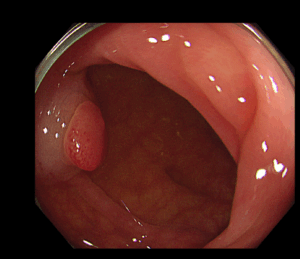

腸の粘膜の一部がイボ状に隆起したものを大腸ポリープといいます。大腸ポリープは組織の違いにより腫瘍性ポリープと非腫瘍性ポリープに大きく分けられ、腫瘍性ポリープはさらに悪性腫瘍(がん)と良性腫瘍(腺腫)に分けられます。

大腸内視鏡検査にてポリープを発見した場合、拡大観察を行い、そのポリープが将来がんになりやすいポリープかどうか判断します。その結果切除が必要と判断された場合には、可能な限り当日ポリープ切除を行います。ポリープが大きい場合、入院して切除が必要な場合、外科的に手術が必要な場合は無理して切除を行わず、安心して治療ができる大きな病院へ紹介する場合もあります。またポリープが多数ある場合は何回かに分けて切除することもあります。